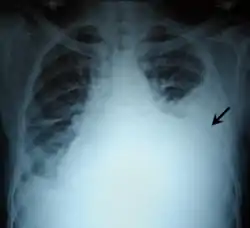

عادة ما يتم تشخيص الارتشاح البِلّوري على أساس السيرة المرضية والفحص السريري، ويتم تأكيد التشخيص بواسطة تصوير الصدر بالأشعة السينية. بمجرد أن يبلغ حجم السوائل المتراكمة أكثر من 500 مل، عادة ما تكون هناك أعراض سريرية عند الكشف على المريض، مثل انخفاض حركة الصدر على الجانب المتضرر، انكتام الصوت عند القرع على الجانب المتضرر، انخفاض أصوات التنفس على الجانب المتضرر، وانخفاض الرنين الصوتي والحسيس (رغم أن تلك علامة غير مُتًّسِقة وغير موثوق بها)، والاحتكاك الجنبي. في الجزء الموجود فوق الارتشاح حيث تكون الرئة مضغوطة، قد يكون هناك تنفس من الشعب الهوائية وصوت ثغاء. في حالة وجود ارتشاح كبير، قد تنحرف القصبة الهوائية بعيداً عن الارتشاح. أظهر استعراض منهجي (2009) تم نشره كجزء من سلسلة "الفحص السريري الرشيد Rational Clinical Examination" في مجلة الجمعية الطبية الأميركية أن انكتام الصوت عند القرع التقليدي هو الأكثر دقة لتشخيص الارتشاح البِلّوري (ملخص نسبة الاحتمال الإيجابية، 8.7 ؛ مدى الثقة 95 ٪، 2.2 -33.8)، في حين أن انخفاض الحفيف الملموس tactile vocal fremitus يجعل وجود الارتشاح البِلّوري أقل احتمالاً (نسبة الاحتمالات السلبية، 0.21، مدى الثقة 95 ٪، 0,12-0,37).[1]

الأشعات

عادةً (في الوضع الطبيعي) لا يمكن رؤية الفراغ الموجود بين طبقتي الغشاء البِلُّوري: الغشاء البِلّوري الجداري (أي المُبَطّن للقفص الصدري) والغشاء البِلّوري الحشوي (أي الذي يغطي الرئة). والارتشاح البِلّوري يتسرب ليملأ الفراغ الموجود بين هاتين الطبقتين. وبما أن الارتشاح البِلّوري له كثافة مماثلة لسوائل الجسم (أو الماء)، فإنه من الممكن رؤيته من خلال صور الأشعات. وبما أن للارتشاح كثافة أعلى من كثافة بقية الرئة (حيث أن الرئة تحتوي على الهواء) فإنه ينجذب إلى الجزء السفلي من التجويف البِلّوري. يتصرف الارتشاح البِلّوري وفقا لديناميات السوائل الأساسية، متسقاً مع شكل الرئة وتجويف الصدر. وإذا كان التجويف البِلّوري يحتوي على كل من الهواء والسائل (hydropneumothorax)، فإن السائل سيكون له مستوى أفقي "fluid level" بدلاً من أن يتسق مع مساحة الرئة.[2] لأشعات الصدر المُلتَقَطة في الوضع الجانبي lateral decubitus position (أي مع وضع المريض على جانبه أثناء التقاط الأشعة) حساسية أكبر، ويمكنها الكشف عن وجود الارتشاح في حال وجود حتى اقل من 50 مل من السوائل. يلزم وجود 300 مل على الأقل من السوائل حتى يتسنى لأشعات الصدر في الوضع القائم (upright position) الكشف عن بعض علامات الارتشاح البِلّوري (على سبيل المثال، التحام الزاوية بين الضلوع والحجاب الحاجز costophrenic angle).